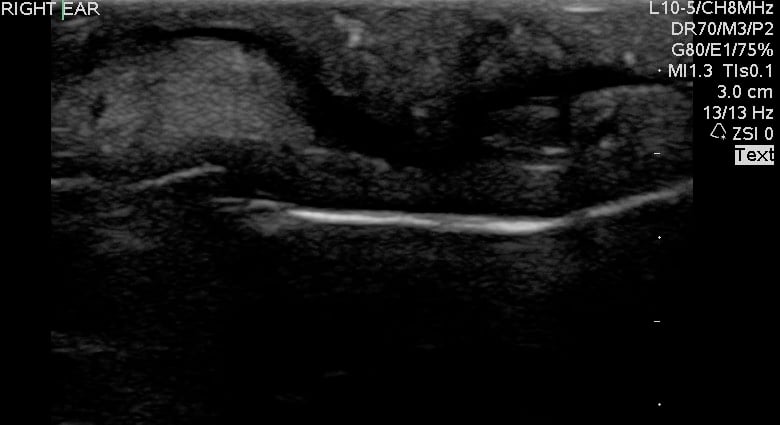

- Figure 5 and 6. Normal Mandible

- Bony structures like mandible, maxilla appear hyperechoic with a posterior hypoechoic acoustic shadow underneath.

- Fat has hyperechoic appearance on ultrasound.

- Muscles are generally visualized as hypoechoic structures but have a more heterogeneous striated appearance.

- Normal Mandible:

Video 4. Normal Mandible